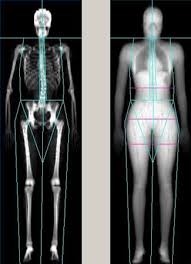

Bone Density Scan

هذا الجهاز يقوم بفحص كثافة العظام , لتجنب امراض هشاشة العظام و التي تحدث مع التقدم في السن و هو عبارة عن جهاز x-ray ثنائي القطب حيث تكون مستويات إشعاعه المنخفضة مساعدة على الكشف عن كثافة العظام , و تكمن اهمية هذا الفحص في تجنب كسور العظام خاصة لدى كبار السن ممن يعانون من العوامل المساعدة على هشاشة العظام , مثل البدانة . قلة الحركة و تاريخ مرضي في العائلة .